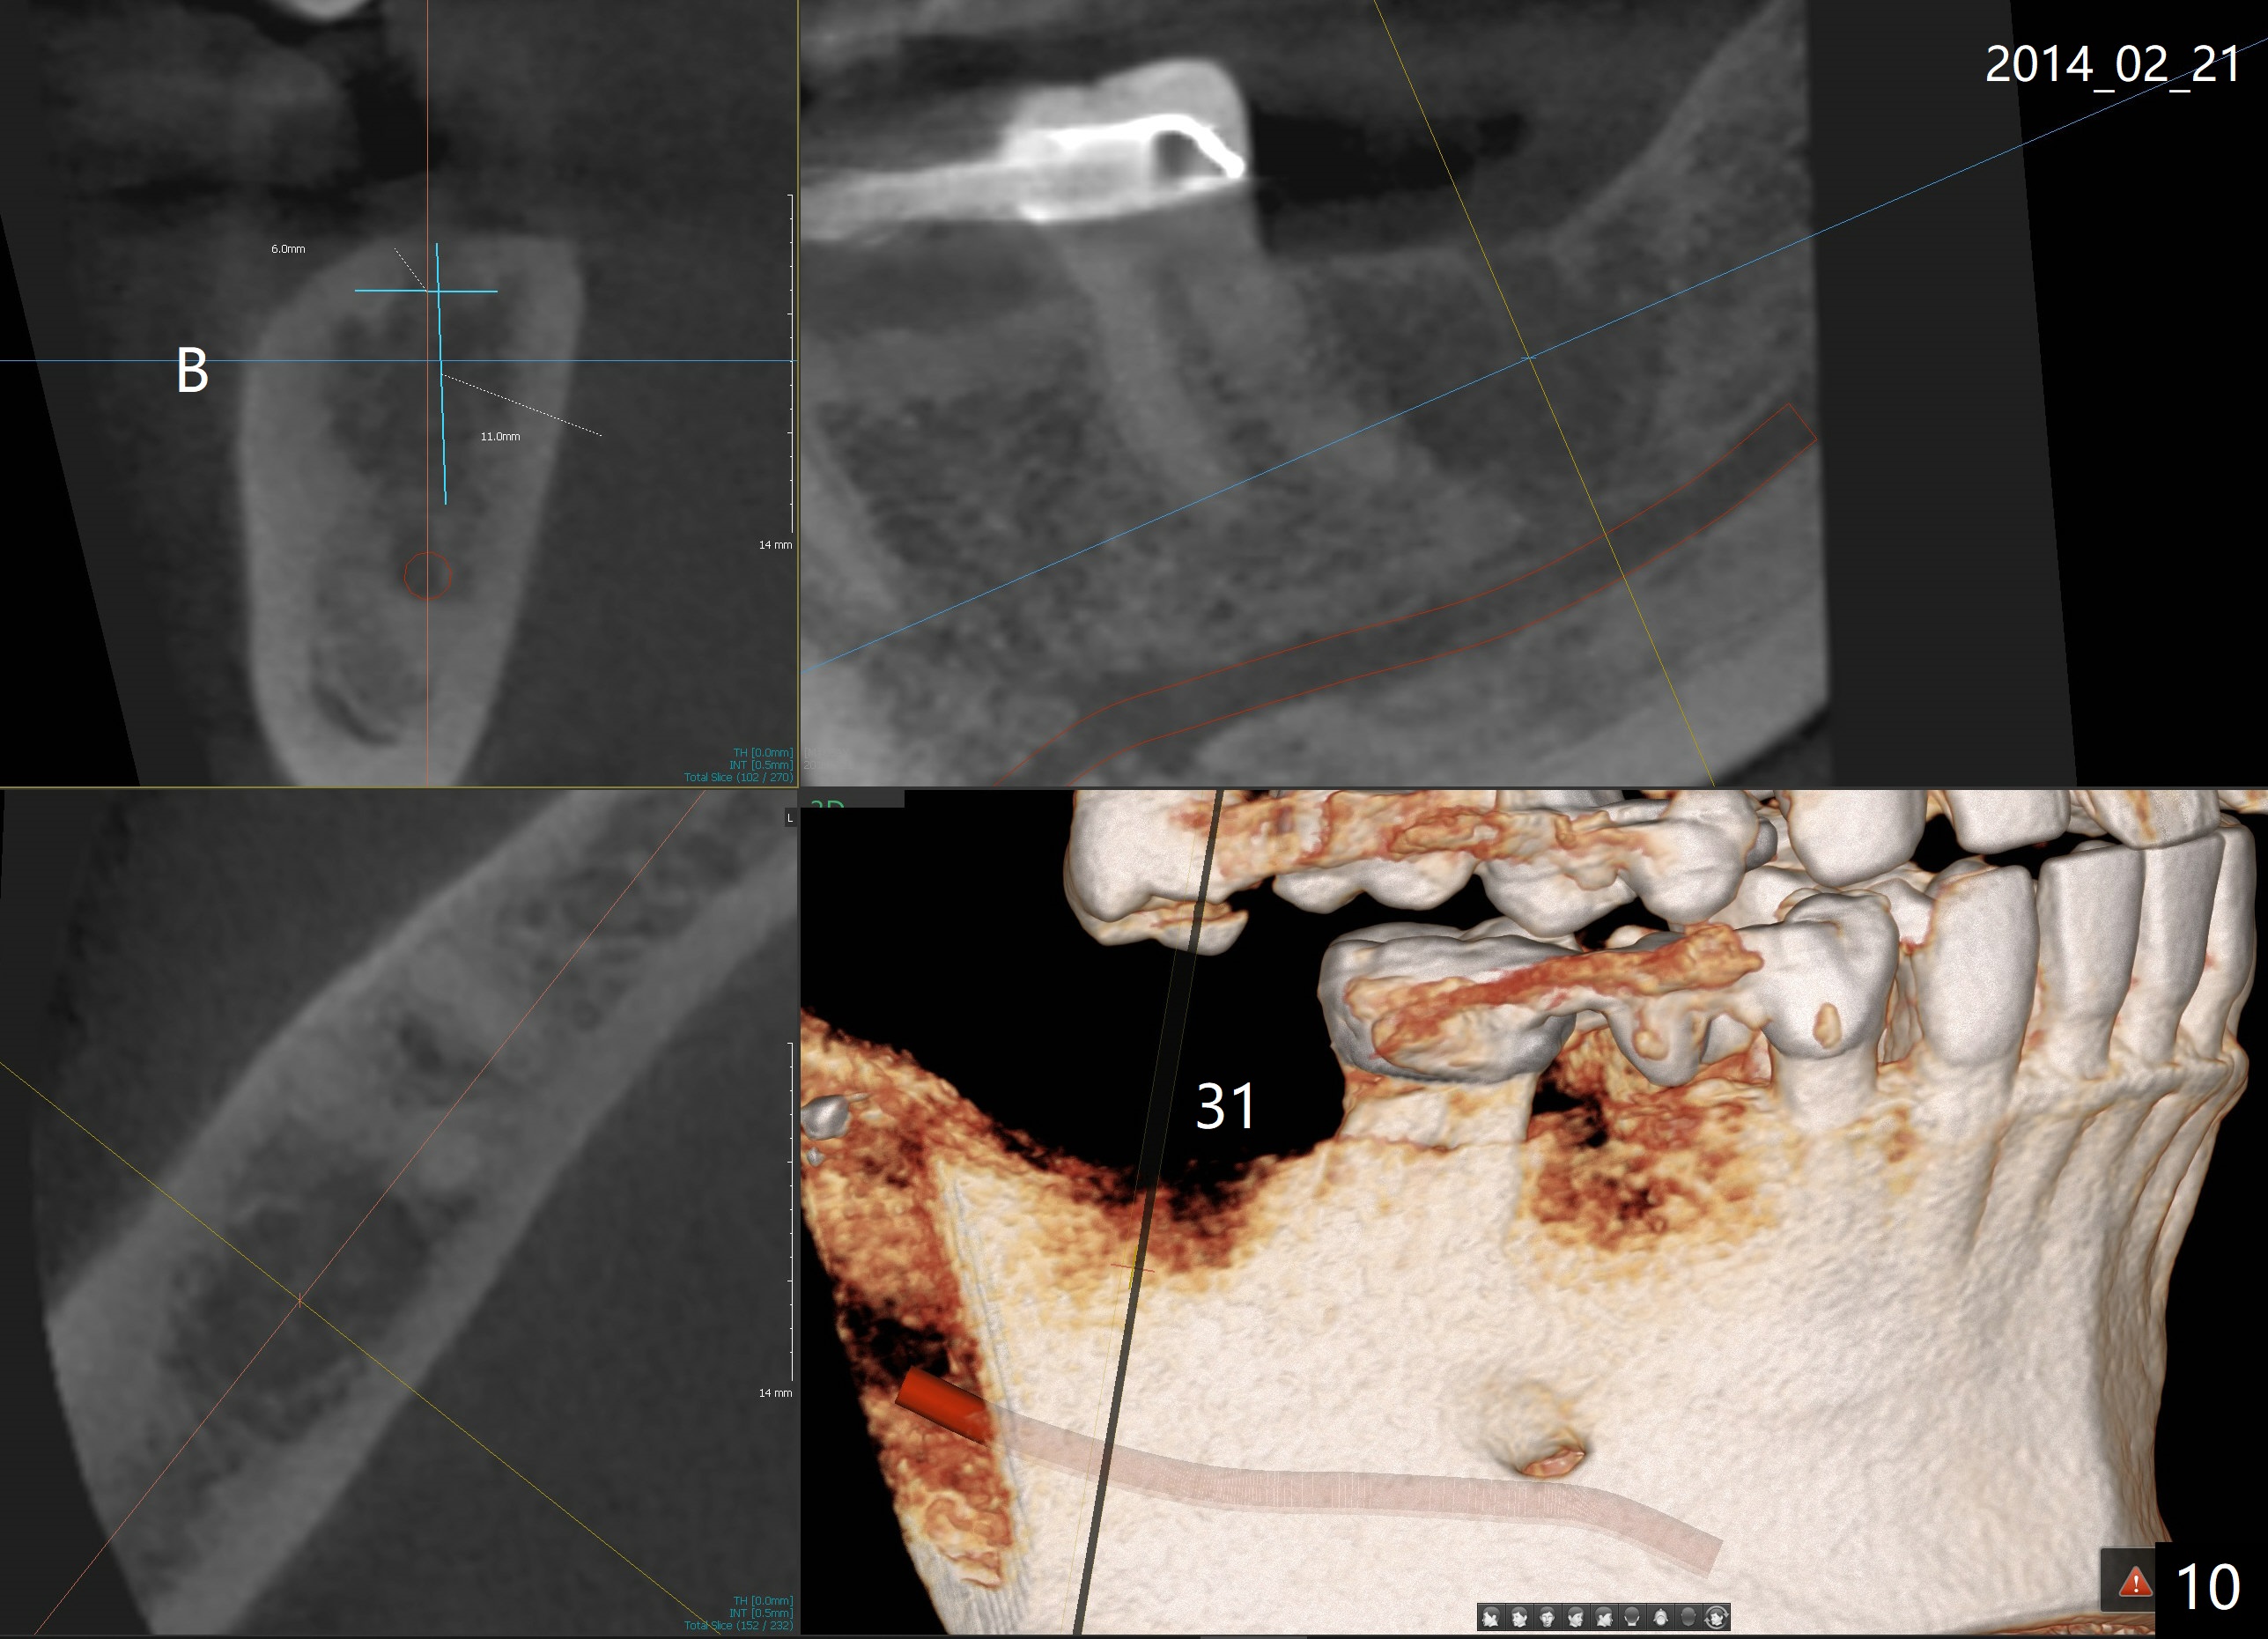

A 51-year-old man requests taking care of hemorrhage and odor associated with the tooth #3 (Fig.1). Due to religious and financial issues, the neighboring teeth will be treated later (supraeruption of #2 (arrow) and periapical radiolucency of #4 (*)). CBCT reveals that the septum of #3 is large enough to hold 4.5 mm implant (Fig.2). In fact osteotomy is created as planned in the septum using drills and taps (Fig.3 after removing 4.5x20 mm tap). Primary stability is obtained with a 4.5x20 mm implant (> 60 Ncm, Fig.4). The gap (*) is bone grafted; an abutment is placed (Fig.5 A); an immediate provisional is fabricated and cemented to cover the socket (Fig.6 P). When the socket heals in 3 weeks postop, the provisional and the abutment are removed for easy oral hygiene. Bone regenerates around the implant 3.5 months postop (Fig.7 *), but the 2nd molar has shifted mesially (arrow), presenting a restoration challenge.